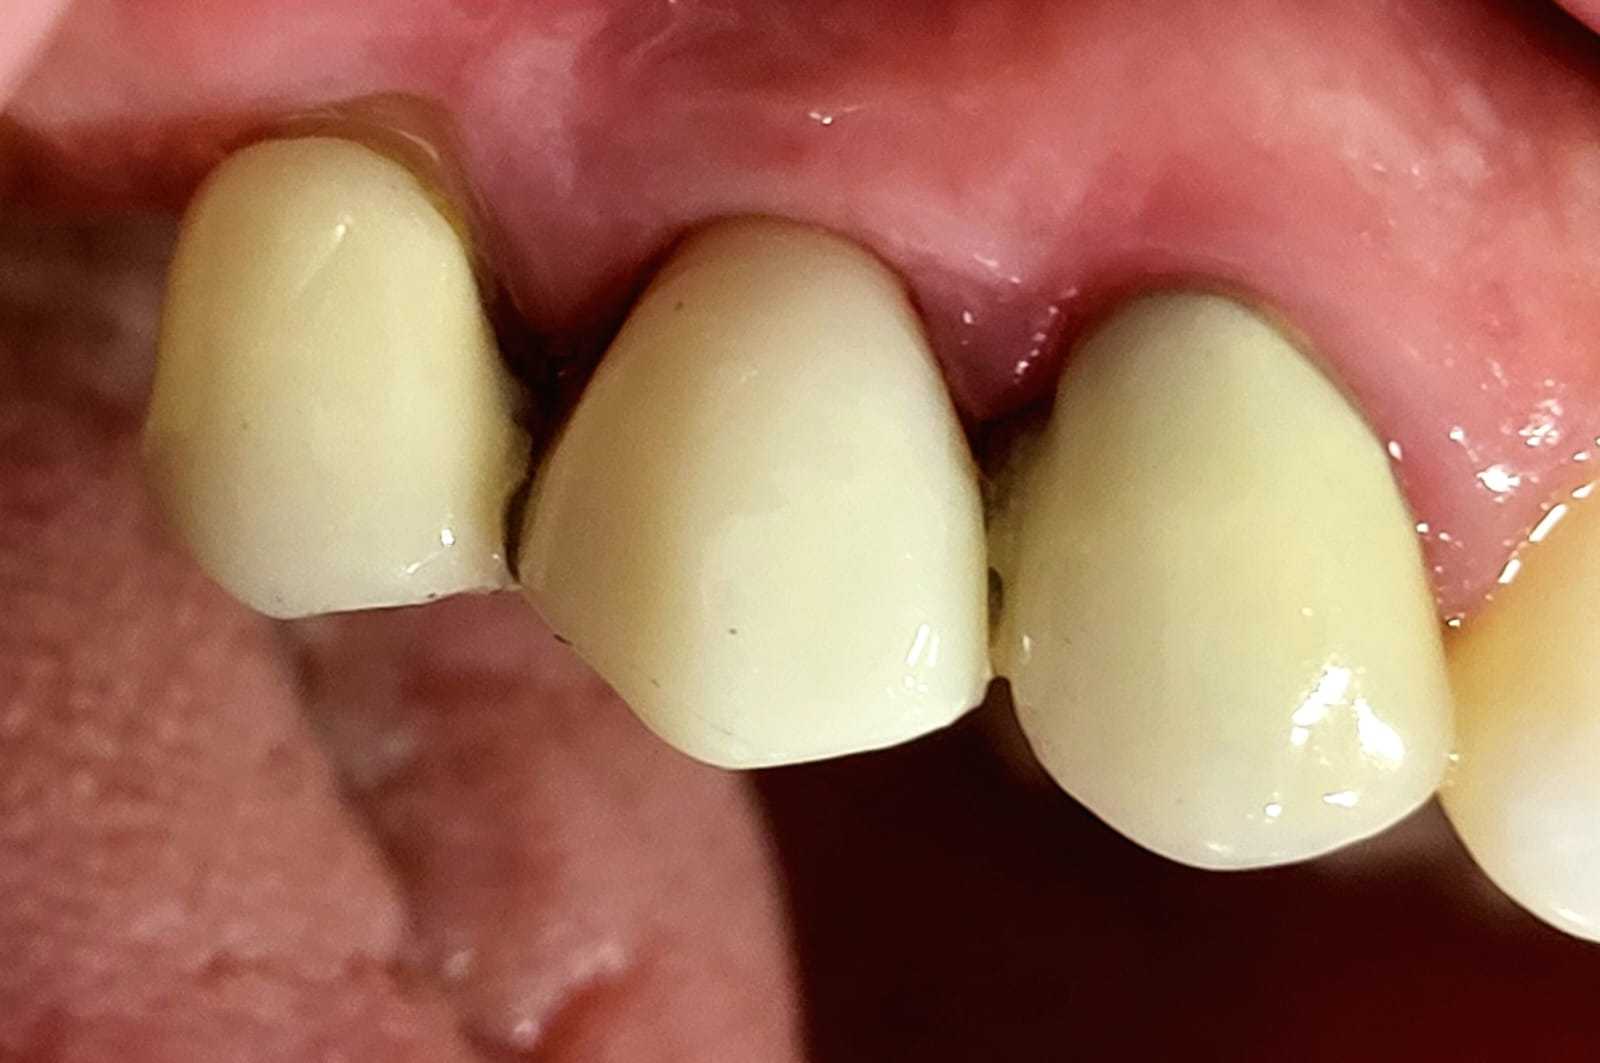

CASO 1

Paciente femenina de 56 años, se presenta a la consulta con puente dental desajustado, con restos alimenticios impactados, se decide realizar un corte de la estructura metálica-porcelana, para conservar piezas restauradas adyacentes, y se coloca un implante dental Marca SIN Implant, realizando provisional para carga inmediata, se espera el proceso de Osteointegración de 4 meses, se observa perfil de emergencia gingival apto, y se procede con la colocación de la corona en Zirconio.